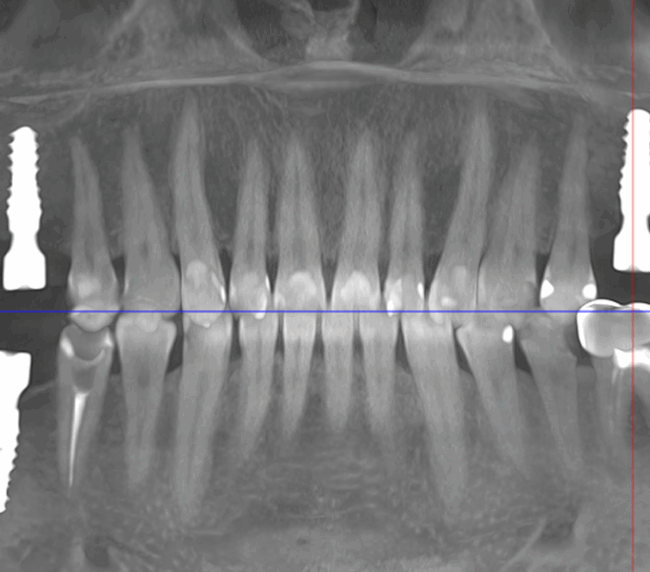

- Consultația inițială și planificarea tratamentului (inclusiv tomografie CBCT)

- Inserarea implanturilor dentare (chirurgie ghidată digital)

- Perioada de osteointegrare (3–6 luni)

- Tehnologie digitală de ultimă generație – scanare 3D, design asistat digital

- Chirurgie implantologică ghidată, minim invazivă